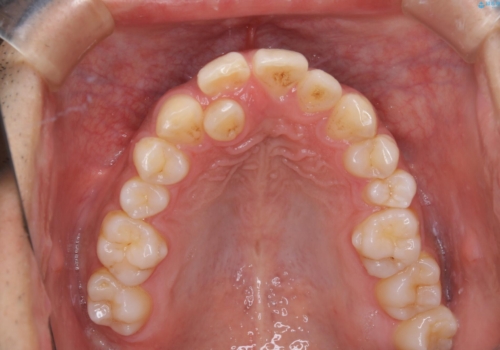

矯正をスタートする前にクリーニングを行いました。PMTC60分コースを行いました。

10年ぶりのクリーニングのため着色や歯石、プラークの量は多めでした。